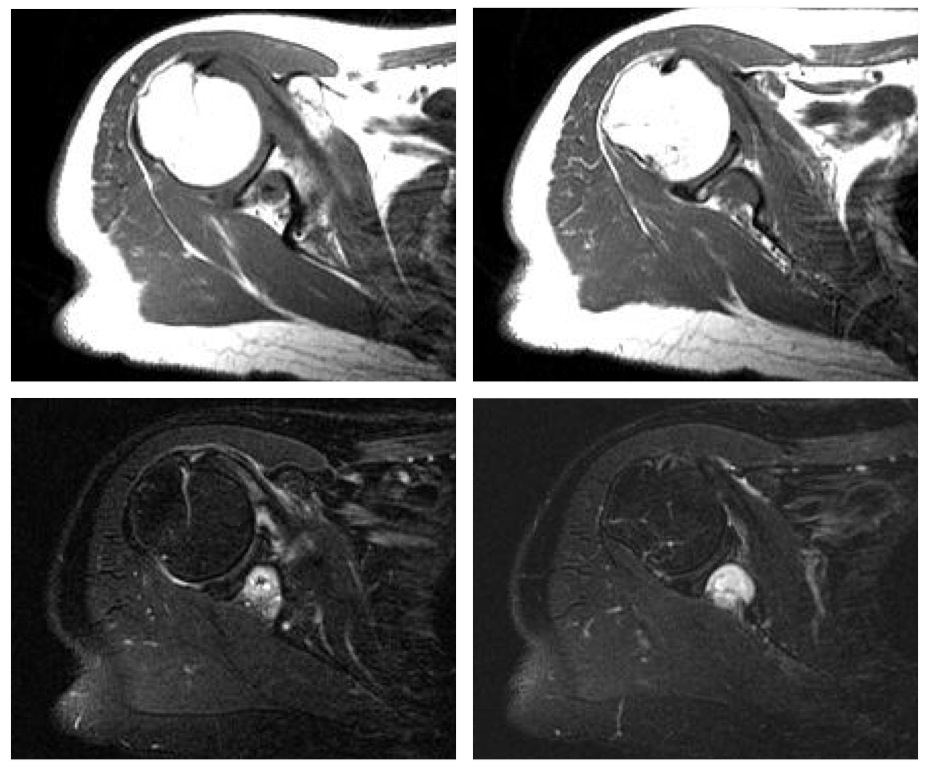

Inflammatory Myofibroblastic Tumor; WHO classify inflammatory myofibroblastic tumor as a distinct borderline lesion with uncertainty as to whether it is reactive or neoplastic; characterized histologically by the presence of acute and chronic inflammatory cells with a variable fibrous response

inflammatory pseudotumor ( RID3860 )